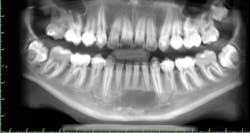

A 14-year-old male presented with a lesion of the anterior mandible first seen on periapical x-rays taken by his general dentist. The patient did not have symptoms and was unaware of any lesion prior to the x-rays.

Clinically, there was no buccal or lingual expansion (figure 1). The patient’s medical history was noncontributory. A CT scan revealed a 1.5 cm x 1 cm well-defined, circular, hypodense area inferior to the lower incisors (figures 2–4).